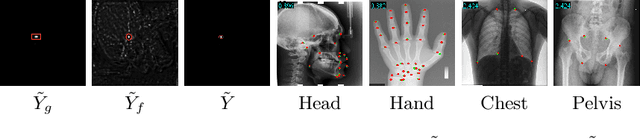

Abstract:One-shot medical landmark detection gains much attention and achieves great success for its label-efficient training process. However, existing one-shot learning methods are highly specialized in a single domain and suffer domain preference heavily in the situation of multi-domain unlabeled data. Moreover, one-shot learning is not robust that it faces performance drop when annotating a sub-optimal image. To tackle these issues, we resort to developing a domain-adaptive one-shot landmark detection framework for handling multi-domain medical images, named Universal One-shot Detection (UOD). UOD consists of two stages and two corresponding universal models which are designed as combinations of domain-specific modules and domain-shared modules. In the first stage, a domain-adaptive convolution model is self-supervised learned to generate pseudo landmark labels. In the second stage, we design a domain-adaptive transformer to eliminate domain preference and build the global context for multi-domain data. Even though only one annotated sample from each domain is available for training, the domain-shared modules help UOD aggregate all one-shot samples to detect more robust and accurate landmarks. We investigated both qualitatively and quantitatively the proposed UOD on three widely-used public X-ray datasets in different anatomical domains (i.e., head, hand, chest) and obtained state-of-the-art performances in each domain.

Abstract:Accurate anatomical landmark detection plays an increasingly vital role in medical image analysis. Although existing methods achieve satisfying performance, they are mostly based on CNN and specialized for a single domain say associated with a particular anatomical region. In this work, we propose a universal model for multi-domain landmark detection by taking advantage of transformer for modeling long dependencies and develop a domain-adaptive transformer model, named as DATR, which is trained on multiple mixed datasets from different anatomies and capable of detecting landmarks of any image from those anatomies. The proposed DATR exhibits three primary features: (i) It is the first universal model which introduces transformer as an encoder for multi-anatomy landmark detection; (ii) We design a domain-adaptive transformer for anatomy-aware landmark detection, which can be effectively extended to any other transformer network; (iii) Following previous studies, we employ a light-weighted guidance network, which encourages the transformer network to detect more accurate landmarks. We carry out experiments on three widely used X-ray datasets for landmark detection, which have 1,588 images and 62 landmarks in total, including three different anatomies (head, hand, and chest). Experimental results demonstrate that our proposed DATR achieves state-of-the-art performances by most metrics and behaves much better than any previous convolution-based models. The code will be released publicly.